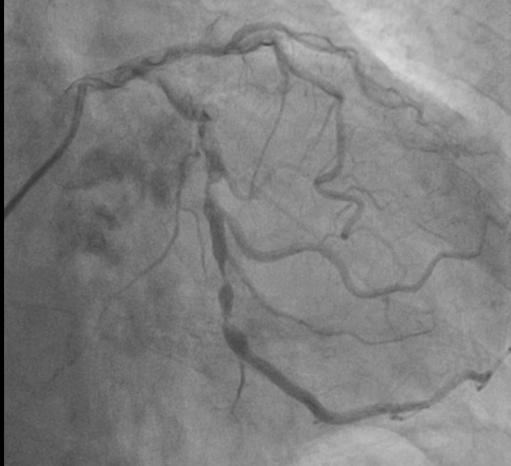

心内科主任医师何晋发现杨爷爷心脏杂音很重,怀疑心脏瓣膜出了问题,经心脏超声检查,果不其然,杨爷爷的心脏有个大“BUG”——主动脉瓣重度狭窄伴中度关闭不全,也就是心脏的阀门坏了,导致他主动脉瓣上下的压差高达70mmHg,而严重的瓣膜病变引发了心脏肥厚、心功能受损,检查还发现他的冠状动脉病变也很严重。

杨爷爷年龄大、心功能差,不能接受外科手术,但如果保守治疗,这类患者的两年生存率不到50%。综合考虑下,何晋主任医师团队多次讨论,最终为杨爷爷制定了经导管主动脉瓣置换及冠脉支架(TAVI+PCI)手术方案,不需要开胸,降低了手术风险。经过精心术前准备,何晋主任医师团队联合心外科、体外循环、麻醉科、介入手术部等多学科,为杨爷爷完成了高难度、超高龄的经导管主动脉瓣置换联合冠脉介入术。

术中,在DSA(数字减影血管造影)严密实时监测下,何晋主任医师从杨爷爷大腿根部股动脉穿刺,通过大血管将主动脉支架瓣膜及装置输送到病变的主动脉瓣位置,缓缓释放支架瓣膜,经过精密调控,支架瓣膜精确植入,原先狭窄的瓣膜口子一下就开通了,术中监测主动脉瓣和心室压差为零。